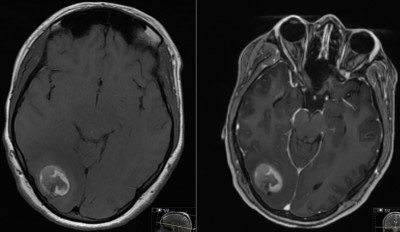

This is a 24 year old female who presented to the ER 2 years prior with first time seizure.

She has mild, intermittent visual disturbance

- Pre-Op